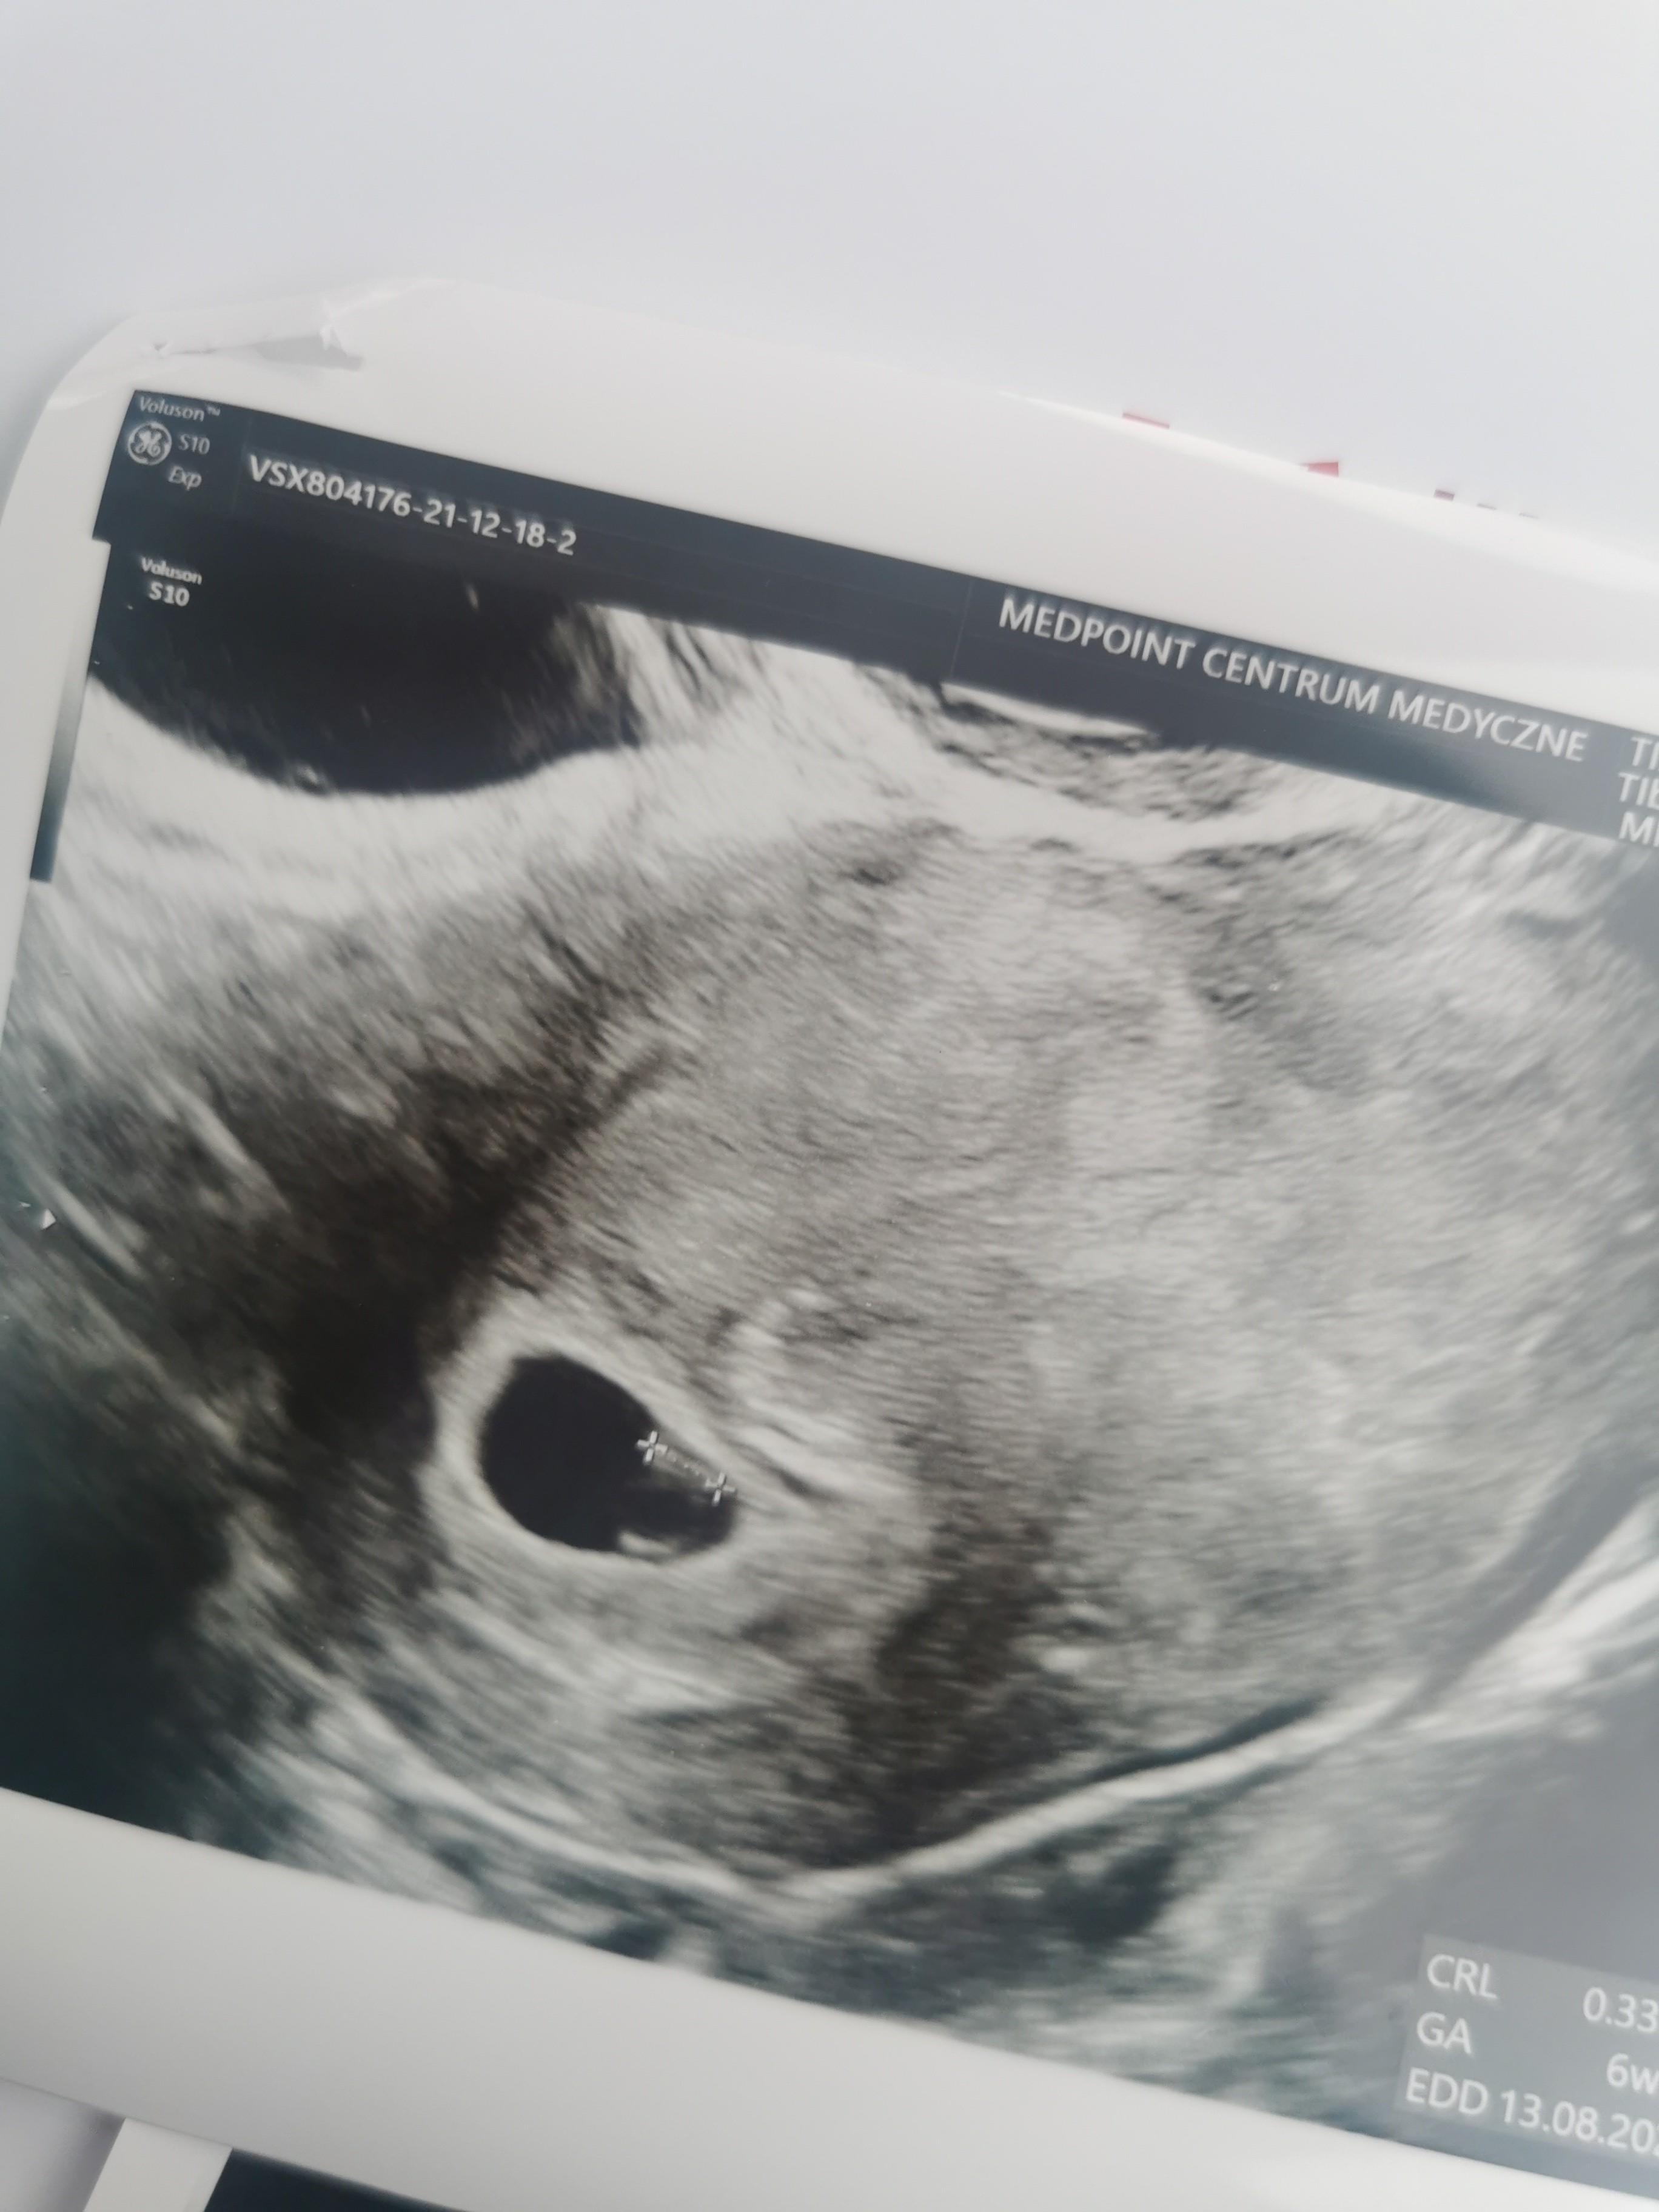

Hej dziewczyny.bylam wczoraj na usg. Mam wyliczone dokladnie 6 tyg wczoraj i mamy pecherzyk 1.1,cialko zolte i zarodek 3.3 z zaczynajacymi sie tlic komorkami i to bylo wlasnie tworzace sie serduszko . Jedyny problem to maly krwiak 1.7x1, ale nie przylega do pęcherzyka i jest dość jasny na obrazir wiec prawdopodobnie sie wchlania. Mialyscie podobny obraz usg? Z zalecen tylko progesteron raz dziennie i nie dzwigac, oszczedzac sie.

• IMG_20211218_133252.jpg

IMG_20211218_133252.jpg

945,1 KB · Wyświetleń: 77